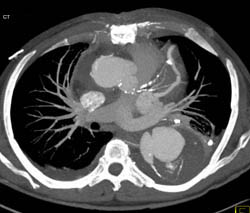

Dilated Aortic Root With Dissection